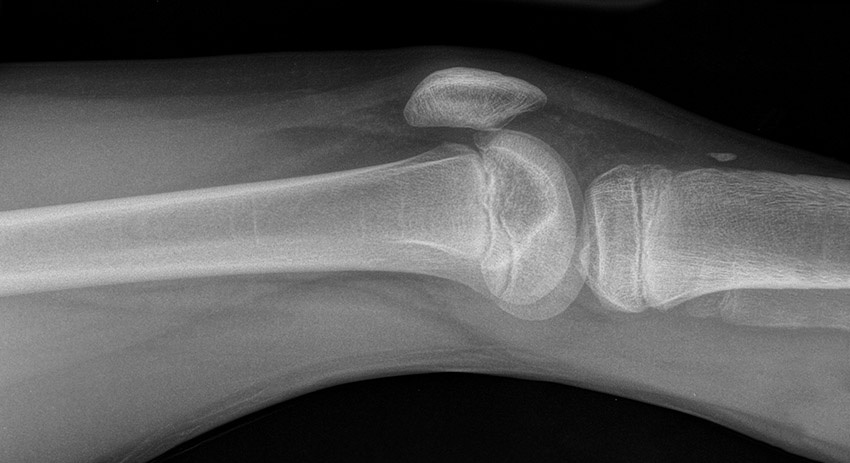

Фото: radiopaedia.org